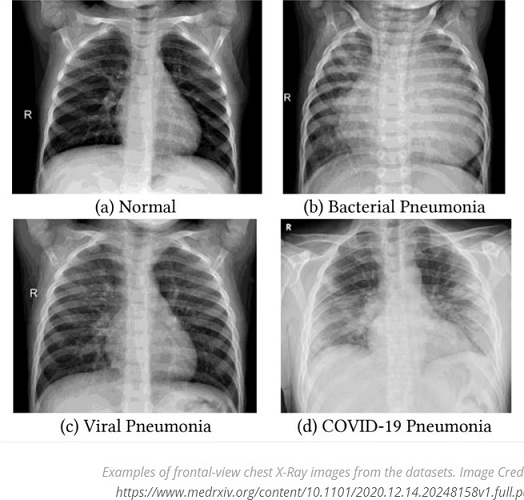

จินตงเยียน ชี้แจงว่าภาพเอกซเรย์ปอดมีฝ้าสีขาวจำนวนมากที่แชร์ทางสื่อสังคมออนไลน์ คือ ภาพเอกซเรย์ปอดที่บ่งบอกการมีอยู่ของรอยโรคชนิดที่เรียกว่า Ground-glass opacity (GGO) ซึ่งมีชื่อในภาษาไทยว่า รอยทึบแบบกระจกฝ้า หรือ ฝ้าจาง

GGO คือรอยโรคในปอดที่พบได้มากในผู้ป่วยโควิด-19 ที่มีอาการไวรัสลงปอด โดยผลเอกซเรย์หรือ CT Scan จะพบฝ้าสีขาวจางที่บริเวณปอด โดยภาพเอกซเรย์ปอดปกติจะเป็นสีทึบ แต่ปอดที่มีของเหลวหรือพังผืดเข้าไปแทนที่อากาศ ทำให้ปอดมีความหนาแน่นที่เพิ่มขึ้น เมื่อทำการเอกซเรย์ปอด ภาพที่ออกมาจะเปลี่ยนจากสีทึบกลายเป็นสีขาวจาง

และภาพเอ็กซเรย์ปอดที่ติดเชื้อ

อย่างไรก็ดี การเกิดฝ้าจางชนิด GGO ไม่จำกัดเฉพาะผู้ป่วยที่ติดเชื้อโควิด-19 เท่านั้น สาเหตุการเกิดฝ้าจางชนิด GGO ที่ปอดมีหลายปัจจัย รวมถึงการติดเชื้อต่อระบบทางเดินหายใจอื่น ๆ รวมถึงการติดเชื้อแบคทีเรียที่ก่อให้เกิดวัณโรคเช่นกัน